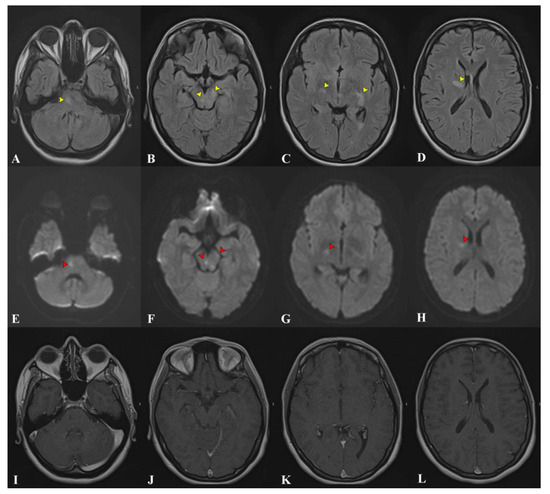

2. Case Presentation